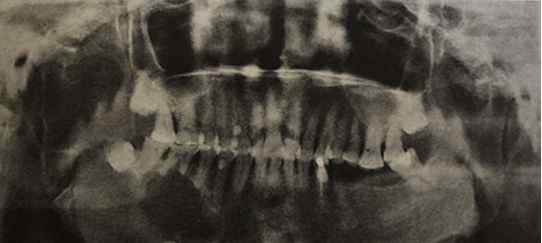

正式介绍 至于口外牙源性肿瘤,成釉细胞瘤和牙源性角化囊性瘤是两种容易混淆的疾病。我们来看看两者的区别。 2019年在教学大纲中增加了《口腔颌面影像诊断学》,即各...